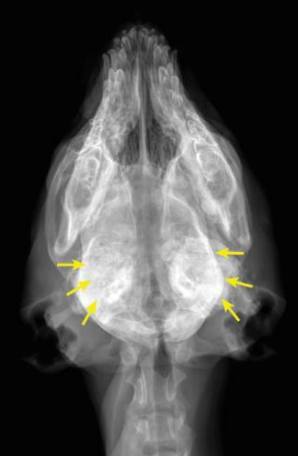

![]() ![]() | - caudal mandibles์ irrecular bone density๊ฐ ์ฆ๊ฐ. - tympanic bullae์ ๋ฐ๋๋ ์ฆ๊ฐ. - 1/3์ ํ์๋ mandible์ ๊ตญํ๋ ๋ณ๋ณ์ ๋ณด์ด์ง๋ง, ์ผ๋ถ ๊ฒฝ์ฐ skull์ ๋ฐ๋ฅ์ ๋ณ๋ณ, ๋๋ ๋๊ฐ๊ณจ ์์ฒด๊ฐ ๋น๋(thickened calvarium). - ๊ฐ๊ฐ ์ฑ์ํด ๊ฐ๋ฉด์, ์๋ก์ด ๋ผ์ ๊ฐ์ฅ์๋ฆฌ๊ฐ ๋งค๋๋ฌ์์ง๊ณ , ๋น์ ์ ๋ถ์๊ฐ ์ค์ด๋ฆ. |

![]() | - tympanic bullae๊ฐ ์ ๋ณด์ผ ์ ๋๋ก ๋๊บผ์์ ธ ์์. |